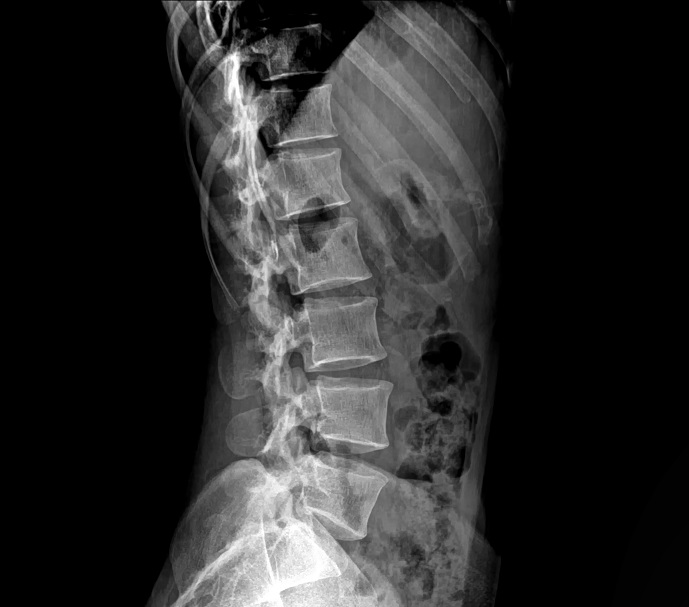

Lumbar Spine Xray

Xray Lumbar Spine Lateral View Aarthi Scans and Labs Lumbar X Ray Dose This projection is utilized in many imaging contexts including trauma, postoperatively, and for chronic conditions. 20 rows this table gives typical effective doses, equivalent periods of natural background radiation and lifetime fatal cancer risks from diagnostic medical exposures. For the most current information, visit radiologyinfo.org. This chart simplifies a highly complex topic for patients’ informational. Radiation dose to adults from. Lumbar X Ray Dose.